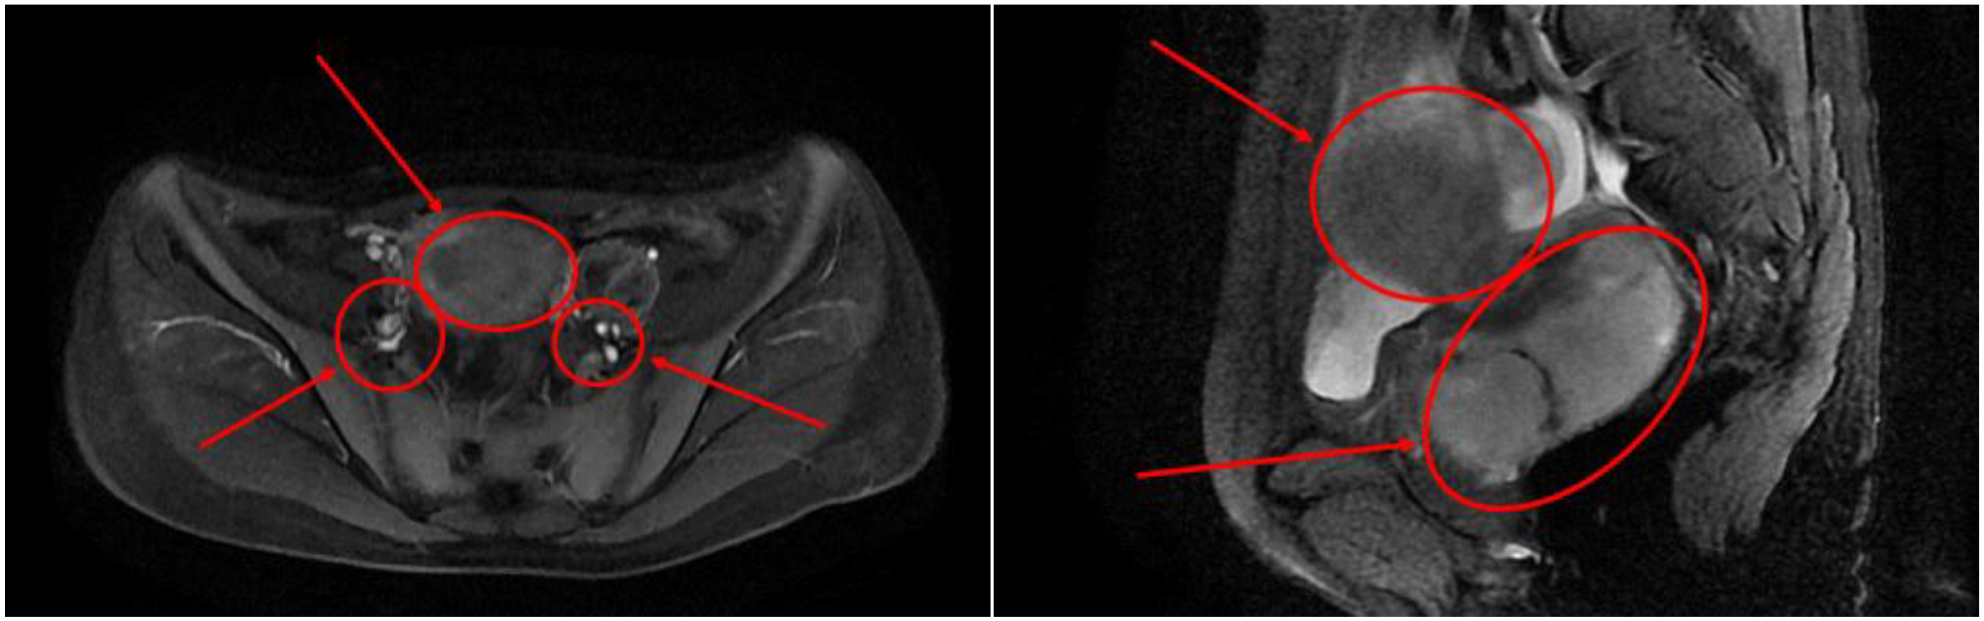

After admission, the patient was found to have tachycardia with a heart rate of 127 beats per minute. Blood cell analysis indicated an elevated white blood cell count of 12.44 x 10^9/L, with an increased percentage of neutrophils at 84.4%. Haemoglobin levels at 82g/L, haematocrit at 31.70%, mean red blood cell volume of 74.4fL, and a platelet count of 729 x 10^9/L confirmed the presence of microcytic hypochromic iron-deficiency anaemia. Stool analysis suggested the positive presence of occult blood. Tumour marker tests for females revealed levels of CA-125 at 117.30U/mL, CA-153 at 46.04U/mL, CA-199 at 74.47U/mL, and Human Epididymis Protein 4 at 572.80pmol/L. Pelvic MRI showed abnormal uterine morphology and signals as shown in Figure 1, suggesting a malignant tumour that had affected the middle and lower parts of the vagina, accompanied by multiple enlarged lymph nodes on both sides of the pelvic wall. As the patient reported no history of sexual activity, a biopsy of the vaginal mass was performed only after the MRI suggested the presence of a malignant tumour. Biopsy histopathological analysis confirmed a diagnosis of carcinosarcoma, with the epithelial component identified as grade 3 endometrioid carcinoma, as shown in Figure 2.

Figure 1

Cross-sectional pelvic MRI and sagittal pelvic MRI findings.

The Multidisciplinary Team (MDT) conducted a comprehensive review of the patient’s MRI, CT, ultrasound and pathological findings. Above studies indicated abnormal uterine morphology and signal changes suggestive of a malignant tumour, with involvement of the middle and lower vaginal segments, as well as multiple enlarged lymph nodes on both sides of the pelvic wall. Given the potentially advanced stage of the disease and the presence of lymphadenopathy, fertility-sparing surgery was deemed unsuitable.